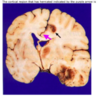

State what type of herniation A-D are [4]

A: **Cingulate** (Subfalcine) B: **Central** (**transtentorial**) C: **Uncal** D: Downward cerebellar (**Tonsillar**)